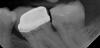

Roman-tim Опубликовано 6 ноября, 2006 Поделиться Опубликовано 6 ноября, 2006 Пишу для того, чтобы другие не попались в руки этим уродам.Итак, брат около месяца назад обратился в стоматологическую клинику "Стелла" (г.Москва). Клиника эта сетевая, имеет по Москве несколько кабинетов. Он обратился в то отделение, которое находится на Шмидтовском проезде (метро "Улица 1905 года"). Попросил запломбировать верхний зуб (то ли 4-ку, то ли 5-ку). Поставили пломбу. Пару дней назад зуб этот, видимо от внутреннего напряжения, раскололся. Раскололся сам, без каких-либо воздействий на него. Славик сказал, что просто во рту что-то щелкнуло, он потрогал языком, а зуб уже пополам. Брат снова позвонил в эту клинику и записался на прием, который и состоялся вчера - 05 ноября 2006 года. Врач зуб осмотрел и сказал, что надо удалять, сделать, якобы, ничего нельзя. Дальше начался кошмар из фильма "Дантист". Они удаляли зуб вчетвером 4,5 часа!!! Раскрошили его полностью, пытались что-то там подпиливать, у них не получалось... В итоге, врач Славику заявил, что два корня он вытащить не может, что-там куда-то "провалилось", что у Вас какая-то не такая надкосница и т.п. Короче, Вам надо ехать в больницу. Вот, мол, адрес. И на бумажке пишет адрес больницы (ул.Фортунатовская, больница № 36, метро "Измайловский парк"), далее, не моргнув глазом, возвращают брату деньги из кассы, дают ему снимок этого несчастного зуба и выпроваживают с настоятельной рекомендацией ехать в эту больницу немедленно. Время на часах 19.00. Нормальный ход врачей-стоматологов, да?!!! Брат по мобиле мне не отвечает, пишет смс, что говорить не может, т.к. ни язык, ни челюсть от уколов не двигаются, просит встретить его около 36-й больницы (а я живу недалеко). Встречаю, время уже около 20.00. Заходим, говорим дежурному врачу в чем проблема. А я напомню: никаких направлений, медзаключений и т.п., кроме снимка зуба, клиника "Стелла" брату не дала. Адрес 36-й больницы был написан на бумажке. Выходит дежурный хирург-стоматолог. Смотрит секунду на снимок, понимающе кивает и брата уводит. Вытащил он ему эти корни за 10 минут!!! В это время вошло: шутки-прибаутки, отвлекающие пациента, очередное обезболивание, кратковременный отдых пациента между двумя манипуляциями (корня было два), дальнейшие рекомендации по уходу за десной, выписка рецепта, краткая характеристика квалификации уродов из "Стеллы". Как сказал этот хирург (дай Бог здоровья нормальным врачам!!), косорукие уроды все это время пытались вырвать не корни, а надкосницу, чем ее основательно повредили. Сами корни торчали рядом, а они их НЕ ВИДЕЛИ. Зато теперь у брата масса впечатлений и дырка в гайморову полость, которая будет теперь долго зарастать.Уважаемые соконфетники! Не ходите лечить зубы в клинику "Стелла", что на Шмидтовском проезде!! Ссылка на комментарий